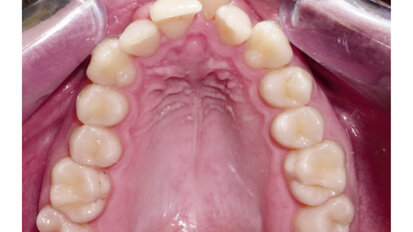

Hybridní terapie alignery